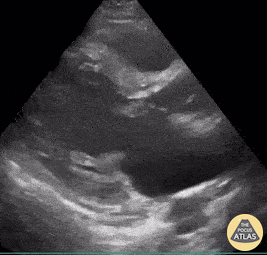

Valvulopathy - Mitral Valve Vegetation

32-year-old woman presented to ED with clinical signs of subacute stroke - confirmed via Brain CT . In the investigation of etiology of cerebral injury, POCUS identified this large hyperechoic vegetation on the mitral valve (seen here both in PLAX and PSAX views). As a result of these images, a diagnosis of infectious endocarditis causing cerebral septic emboli injury was considered. Renato Tambelli; @JediPocus Emergency Physician (HCFAMEMA /Sao Paulo, Brazil)